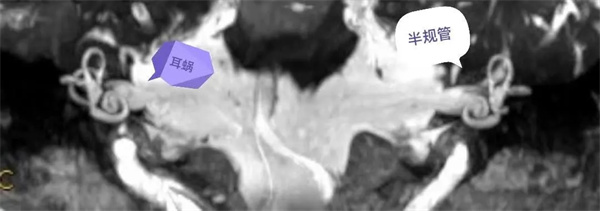

圖1:MIP圖,橫軸位清晰顯示雙側(cè)內(nèi)耳道,耳蝸,半規(guī)管全貌。

圖2:MIP圖,冠狀位清晰顯示雙側(cè)內(nèi)耳道,耳蝸,半規(guī)管全貌。